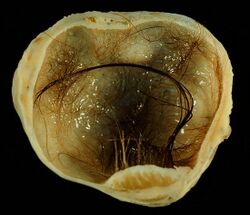

Immature, or solid, teratomas are the most common type of ovarian germ cell tumor, making up 40–50% of cases. Teratomas are characterized by the presence of disorganized tissues arising from all three embryonic germ layers: ectoderm, mesoderm, and endoderm; immature teratomas also have undifferentiated stem cells that make them more malignant than mature teratomas (dermoid cysts). The different tissues are visible on gross pathology and often include bone, cartilage, hair, mucus, or sebum, but these tissues are not visible from the outside, which appears to be a solid mass with lobes and cysts. Histologically, they have large amounts of neuroectoderm organized into sheets and tubules along with glia; the amount of neural tissue determines the histologic grade. Immature teratomas usually only affect one ovary (10% co-occur with dermoid cysts) and usually metastasize throughout the peritoneum. They can also cause mature teratoma implants to grow throughout the abdomen in a disease called growing teratoma syndrome; these are usually benign but will continue to grow during chemotherapy, and often necessitate further surgery. Unlike mature teratomas, immature teratomas form many adhesions, making them less likely to cause ovarian torsion. There is no specific marker for immature teratomas, but carcinoembryonic antigen (CEA), CA-125, CA19-9, or AFP can sometimes indicate an immature teratoma.[33]

Mature teratomas, or dermoid cysts, are rare tumors consisting of mostly benign tissue that develop after menopause. The tumors consist of disorganized tissue with nodules of malignant tissue, which can be of various types. The most common malignancy is squamous cell carcinoma, but adenocarcinoma, basal-cell carcinoma, carcinoid tumor, neuroectodermal tumor, malignant melanoma, sarcoma, sebaceous tumor, and struma ovarii can also be part of the dermoid cyst. They are treated with surgery and adjuvant platinum chemotherapy or radiation.[33]